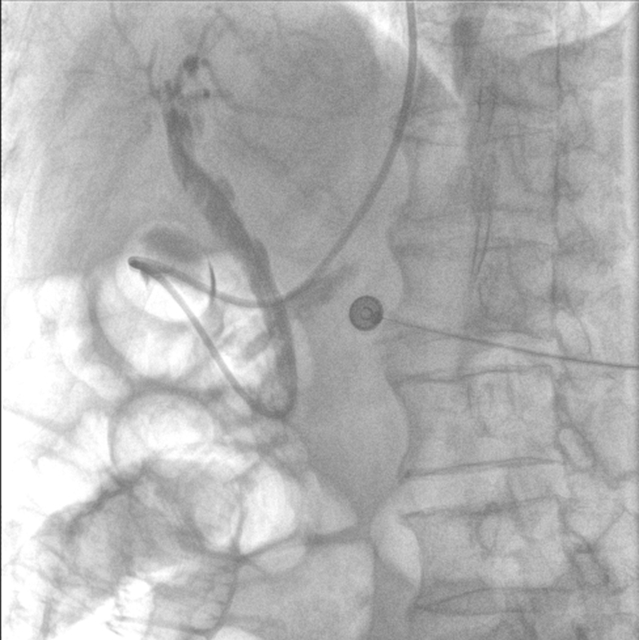

完善相关检查后,肝胆胰外科医生团队立即为张大爷实施了急诊内镜逆行胰胆管造影(ERCP)。

内镜到达十二指肠乳头时,切开乳头的瞬间,大量白色脓液喷涌而出(证实胆道高压、感染极重);随后用球囊扩张乳头(扩大开口),顺利取出嵌顿的结石。

术后,放置鼻胆管持续引流脓性胆汁(当天引出300ml浑浊胆汁)。

3.精准:“可视化”操作降低风险

内镜逆行胰胆管造影全程在X光和内镜直视下完成,医生能清晰看到结石位置、乳头形态,避免盲目操作。即使结石嵌顿严重(像"卡在墙缝里的石块"),也能通过球囊扩张或机械碎石取出,成功率高达90%以上。